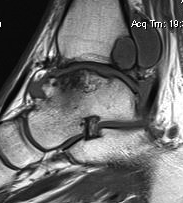

Ankle osteoarthritis

• Background